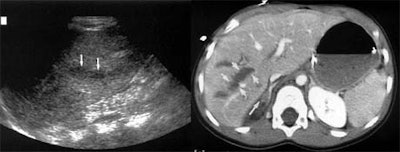

In all, 75 patients (10%) had intra-abdominal injuries. Ultrasound detected free fluid in 42 patients (56%).

For the detection of free fluid with ultrasound, "our sensitivity was actually fairly low," McGahan said. "We had 43 true positives, 36 false negatives, overall sensitivity of 56%. No matter what standard you look at, specificity was high," in the range of 98%.

![]() |

Ultrasound detected organ injuries in 9 patients (12%) in which no free fluid was identified. These included 3 splenic injuries, 3 liver injuries, and 3 renal injuries, for an approximate sensitivity of 70%, McGahan said. The inclusion of sonographic identification of parenchymal organ injury increased the sensitivity of ultrasound to 86%, with overall accuracy of 96%.